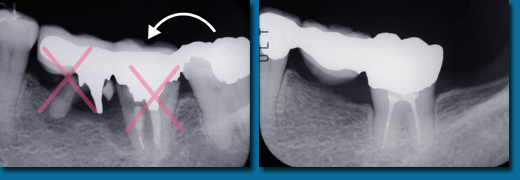

歯並びが悪くなってから治療することを歯列矯正といいますが、乳歯の頃から出てくる歯並びが悪くなる兆候を早期に発見しそれを改善しながらきれいな歯並びの永久歯にしていくことを咬合育成といいます。専門的には歯列矯正と咬合育成は別の物と区別されています。咬合育成は歯並びの予防と考えられ当医院では積極的に取り組み、多くの歯並びの良い子供が育っています。写真の左は乳歯の時、右が永久歯になった時のものです。

咬合育成でおこなうひとつの治療に顎を拡げて永久歯の入るスペースを作るというものがあります。

歯並びの悪い人の多くは顎が小さくて永久歯が並びきらないことが原因になっています。

成長が終わってから矯正治療を受けた方のほとんどが永久歯を4本抜歯してスペースを作って歯並びをきれいにしますが高齢になって歯を失いはじめると最初から歯が4本少ないことは咀嚼をする上でかなりのハンディキャップになります。

なるべく歯を抜かないできれいな歯並びにするには成長期に骨を刺激し、顎を拡げることです。

乳歯から永久歯への生え替わりは6歳くらいから上下の前歯4本から始まり、そして10歳ころから犬歯、奥歯と生え替わり12歳ころで終わります。

はじめに前歯の4本がきれいに並ばなければその後の犬歯、奥歯の生え替わりで歯並びはどんどん悪くなってしまいます。

そのため上下の前歯4本が生え替わる時期に顎を拡げ、きれいに並べておく必要があります。

あまり知られていませんが永久歯の奥歯は乳歯よりも小さいので前歯4本がきれいに並んでいれば奥歯はほとんどがきれいに並びます。

乳歯の時からスペース不足の傾向はでているので個人差はありますが5歳くらいからなるべく早く開始すると安心です。

遅くても8歳になる前には始めなければこの治療法は選択できません。